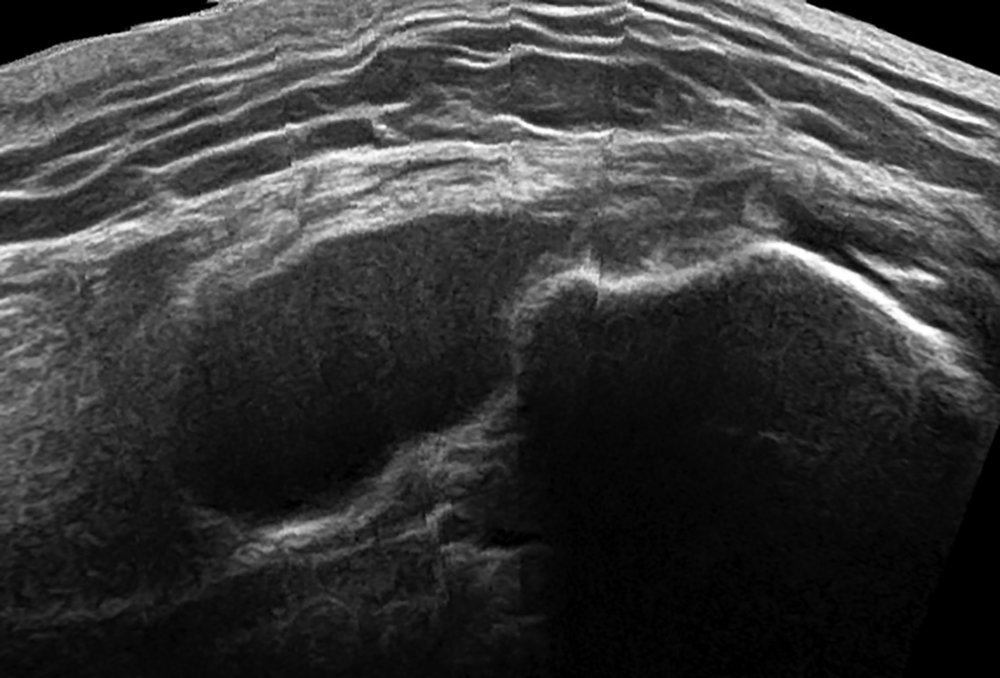

Sports and Spinal Physiotherapists delivering outstanding treatment and rehabilitation